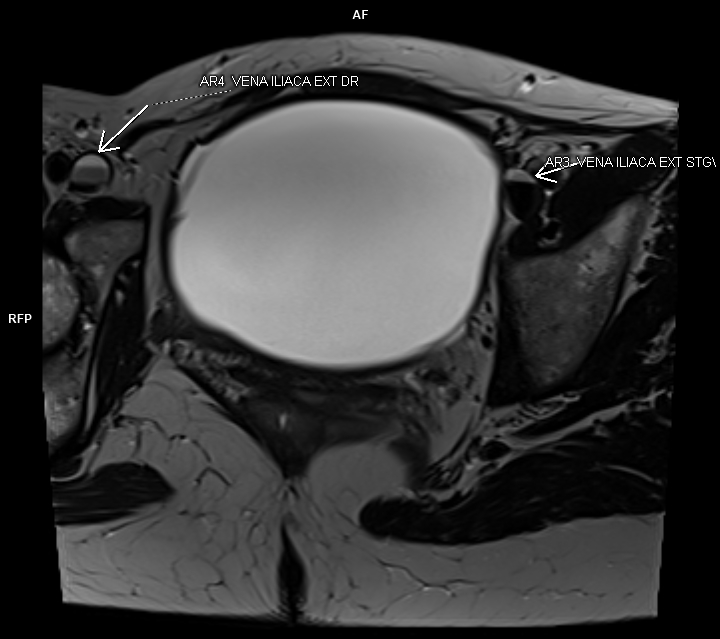

Figura 1: oblic-axial T2

Discuţie caz nr 100: Leziune expansivă voluminoasă este evidențiată la nivel pelvin cu apartenența ovariană dreapta. Formațiunea nu prezintă restricție de difuzie a apei, are conținut cu semnal lichidian, fără priză de contrast și perete subțire cu priză de contrast. Leziunea  nu conține porțiuni tisulare și nici septuri, amprentează dinspre superior vezica urinară și produce compresia venelor iliace cu un aspect tristratificat venos în amonte (vezi figurile 1 și 2). Pacienta a fost operată și diagnosticul a fost de chistadenom.